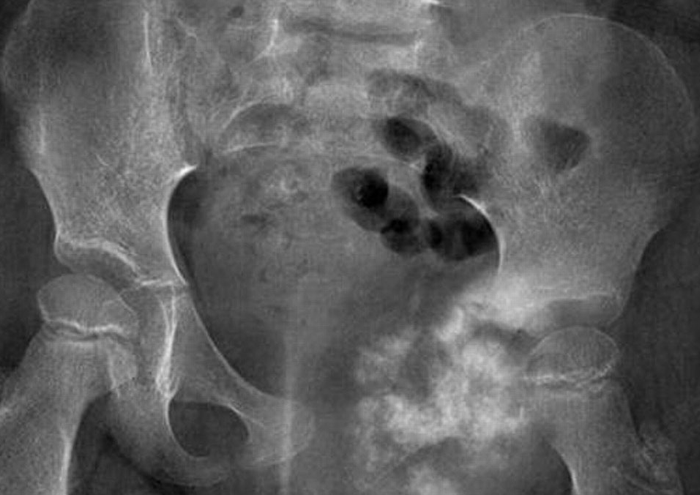

مولتیپل میلوم (Multiple Myeloma)

مولتیپل میلوم یک بیماری هماتوآنکولوژیک است که به شکل ضایعات استخوانی در لگن ظاهر میشود. سلولهای پلاسما تکثیر یافته باعث تخریب استخوان میشوند و بیمار، علائمی از جمله درد استخوان، شکستگی پاتولوژیک و ضعف عمومی را تجربه میکند. تشخیص این نوع سرطان لگن در زنان و مردان، با کمک روشهای مانند تصویربرداری پیشرفته CT، MRI، PET‑CT و بیوپسی مغز استخوان امکانپذیر است. پزشک هم ممکن است از درمانهایی مانند تجویز داروهای ضدمیلوم، داروهای ضداستئوکلاست و در موارد ضروری تثبیت جراحی یا ارتوپدی کمک بگیرد.